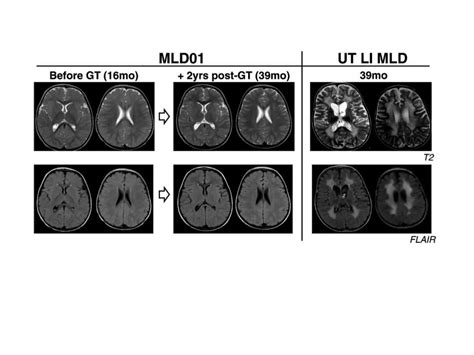

Diagnosing White Matter Disease typically relies on advanced imaging techniques rather than just clinical observation. Physicians look for specific patterns of damage that distinguish this condition from others like Alzheimer’s or stroke.

MRI (Magnetic Resonance Imaging) The gold standard for identifying white matter hyperintensities (bright spots on the scan indicating damage).